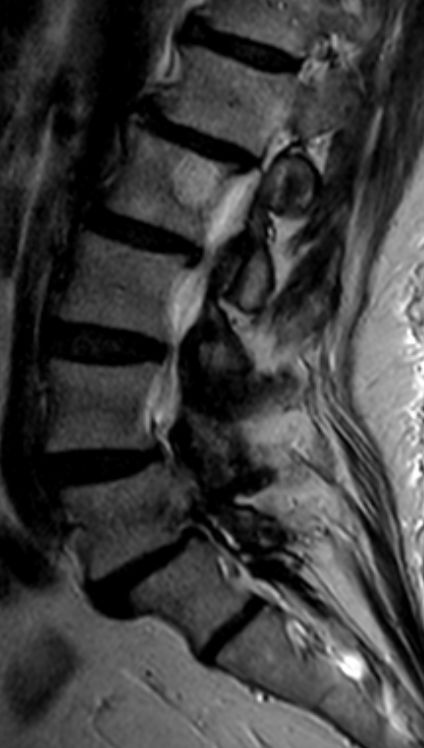

| Knochen | 63-jährige korpulente Frau mit chronischen LWS-Beschwerden. MRT im T2W TSE-Bild:

Haemangiom in L2. (Auch in L3 hier nicht sichtbar.)![]() |

MRT im T1W TSE-Bild.![]() |